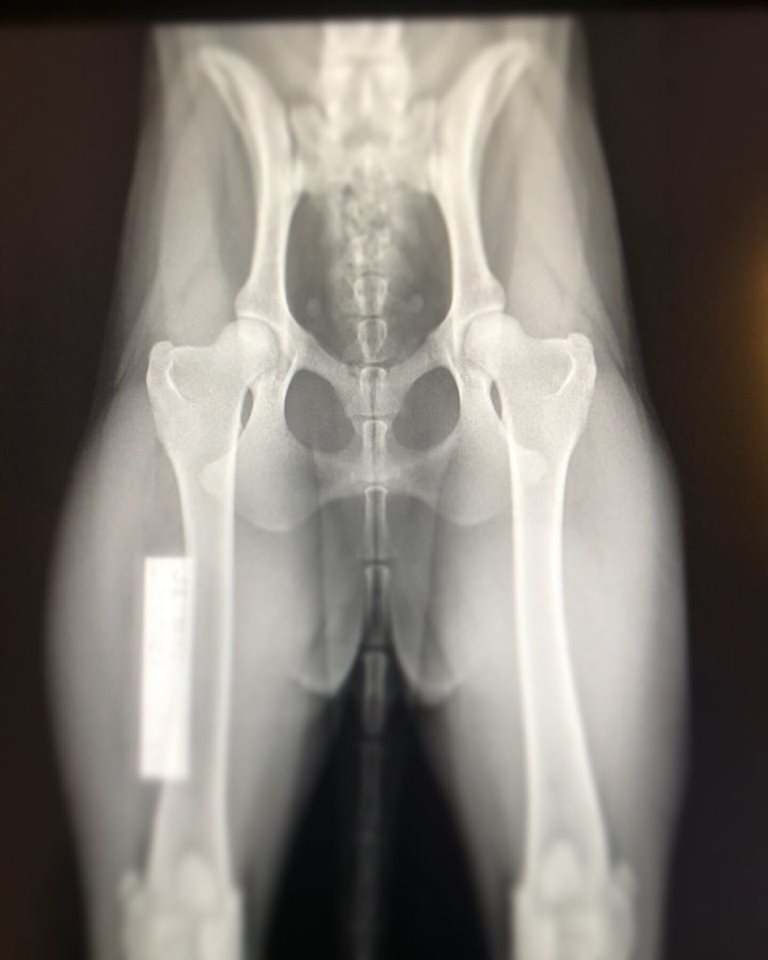

Röntgen

Kliniken är utrustad med digitalröntgen. Metoden innebär minimal strålning för djuret och är också skonsam för miljön.

En röntgenundersökning kan ge mycket information vid många olika tillstånd, som till exempel hältor, lunglidanden, eller om man oroar sig för att djuret ätit något som kan ha fastnat i mage eller tarm.

Från och med sjunde dräktighetsveckan kan dräktighet, inklusive antal foster, fastställas med hjälp av röntgen. Vill man veta om tiken/katten är dräktig tidigare är ultraljudsundersökning möjlig från ca dag 25. Vi utför också röntgen av höft-, armbågs- och knäleder enligt Svenska Kennelklubbens direktiv.

Råda bots sköterskor har stor vana av dessa undersökningar och gått diverse utbildningar, både inom veterinärmedicin och inom SKKs regi. För att läsa mer om röntgen inom Svenska Kennelklubben, tryck på länken här under. SKK Röntgen Inför SKK röntgen så måste beställa och betala avläsning själv, detta utförs inte hos oss på kliniken. Tryck på länken här under och följ instruktioner.